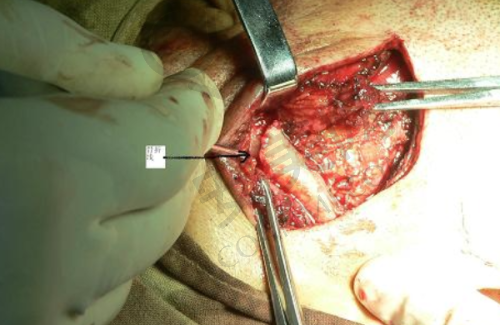

终于到了种植牙手术的那天,我心里还是有点紧张的。医生给我打了局部麻醉,在麻醉生效后才开始手术。整个手术过程中,我并没有感觉到明显的疼痛,只是能感觉到医生在操作。医生的技术非常娴熟,动作特别轻柔,每一个步骤都特别精细。手术持续了大概一个多小时,结束后,医生详细地跟我交代了术后的注意事项,比如要注意口腔卫生、避免吃辛辣刺激的食物等。术后,麻醉药效过了之后,确实有一些轻微的疼痛和肿胀,但都在可以忍受的范围内。医生给我开了一些消炎药和止痛药,按照医嘱服用后,疼痛和肿胀特别快就缓解了。

宿州康桥口腔医院的种植牙技术有特别多特色之处。首先,他们采用的是精良的种植系统,这些种植体的材质非常好,生物相容性高,能够与牙槽骨更好地结合,提高种植牙的成功几率。其次,医院拥有专精的医生团队,他们都有丰富的临床经验,能够根据患者的具体情况制定更适合的种植方案。而且,医院还引进了精良的数字化种植技术,通过计算机模拟种植过程,能够更精细地确定种植体的位置和角度,减少手术创伤,缩短手术时间。另外,医院的服务也非常贴心,从术前的询问、检查,到术中的治疗,再到术后的回访和维护,都有专人跟进,让患者感受到全方面的关怀。